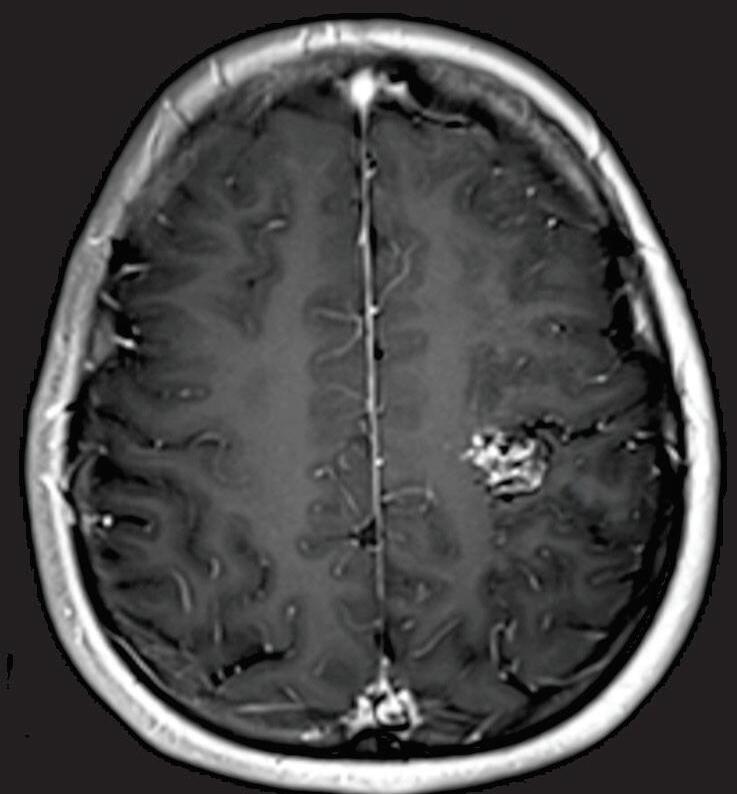

A suspeita diagnóstica das MAVs geralmente é feita por meio de métodos não invasivos de aquisição de imagem, tais como tomografia computadorizada (TC), angiotomografia, ressonância magnética (RNM) e angiorressonância, contudo, as informações anatômicas vasculares necessárias para o planejamento e a execução terapêutica demandam geralmente do estudo dinâmico da angioarquitetura da MAV pela arteriografia cerebral, considerado o exame padrão-ouro para o diagnóstico (Figs. 1-21 e 1-22).35

Fig. 1-21. TC de crânio sem contraste em cortes (a) axial e (b) coronal. (c) RNM encéfalo T1 com contraste axial. (d) Angiorressonância arterial sagital. Arteriografia digital em (e) AP e (f) perfil, demonstrando MAV não rota localizada no giro pré-central à esquerda nutrida por ramos da artéria cerebral média e caloso marginal esquerdo. Setas azuis apontando para o nidus da MAV.

visualização da anatomia cerebral, das alterações parenquimatosas, bem como: gliose peri ou intranidal, atrofia parenquimatosa com dilatação focal do sistema ventricular, possibilita a diferenciação da hemorragia aguda da crônica (visualização da hemossiderina nas sequências gradiente eco [GRE] e hidrocefalia (secundária a hemorragia prévia e ou compressão do sistema ventricular por veias de drenagem dilatadas).35

A utilização de técnicas avançadas, como a tractografia (Fig. 1-23), reconstruções 3D, permitem um estudo detalhado de estruturas anatômicas e sua relação com as patologias cerebrais, facilitando assim o planejamento cirúrgico. A tractografia, uma técnica de ressonância magnética, permite estudar os tratos da substância branca do cérebro, mostrando sua posição, anatomia e integridade, por meio da análise do movimento das moléculas de água no tecido cerebral.35

Dentre os estudos funcionais de neuroimagem podemos citar a ressonância magnética funcional (fMRI), que permite a identificação de áreas ativas do cérebro enquanto o paciente realiza tarefas específicas, como movimentos, fala ou reconhecimento visual; orientando assim, com maior precisão, a abordagem cirúrgica.35